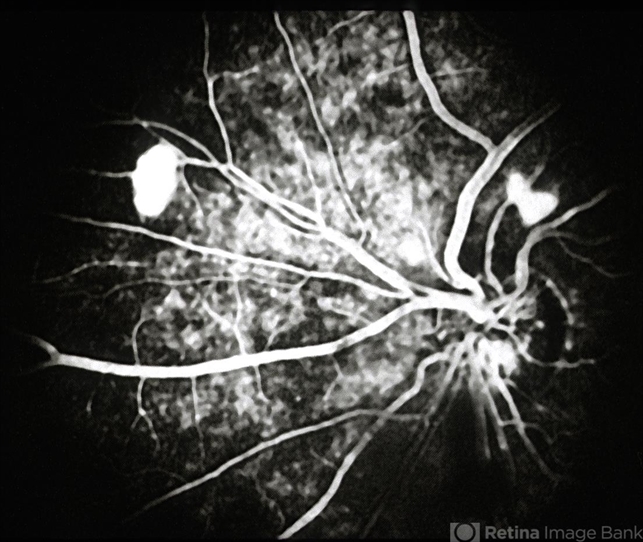

- retinal neovascularization

- early-phase FA of optic disc